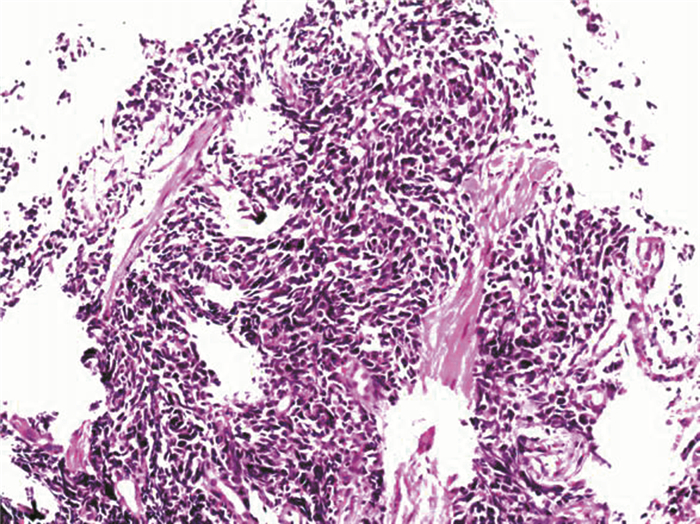

血常规:中性粒细胞百分比84.1%、血小板49×109/L,余正常。尿常规、粪常规、甲胎蛋白、癌胚抗原、糖类抗原199、甲状腺功能、CRP、血清降钙素原正常。乙型病毒性肝炎 (乙肝) 三对、丙型病毒性肝炎 (丙肝) 病毒抗体、抗HIV、血幽门螺杆菌抗体、梅毒特异性抗体、抗核抗体均阴性。A型血、Rh (+)。肝功能:总胆红素44.3 μmol/L、直接胆红素12.1 μmol/L、间接胆红素32.2 μmol/L、ALT 46 U/L、AST 63 U/L、碱性磷酸酶179 U/L、γ-谷氨酰转移酶103 U/L。电解质:钾3.4 mmol/L。凝血常规:凝血酶原时间16.3 s、国际标准化比率1.34、部分凝血活酶时间55.2 s。X线胸片、胸部CT示双肺未见明显异常。上腹部CT示肝硬化、脾大、门脉高压、腹水、胆囊结石并胆囊炎。腹部彩超示肝硬化、脾大、腹腔积液、门静脉内径增宽、胆囊继发改变、胆囊多发结石。胃镜示食管静脉曲张 (轻度)、食管肿物 (表面光滑,未见糜烂及溃疡形成),见图 1。入院诊断“肝硬化失代偿期 (酒精性)、门脉高压症、脾功能亢进症”基本明确,但此次胃镜下发现食管中上段肿物,性质尚不明确,行超声胃镜示食管固有肌层肿物 (考虑间质瘤),见图 2。病理检查结果示 (食管) 小细胞恶性肿瘤、结合免疫组织化学 (组化) 符合小细胞癌。免疫组化结果示CgA (+),CK5/6(-),CKpan (+),K1-67(+50%~75%),LCA (-),NSE (+),P63(-),Syn (+),TTF-1(+),见图 3

图 1 PESCC患者胃镜图

本例患者为65岁老年男性,主要临床症状为腹胀、腹水、纳差、乏力等肝硬化失代偿期表现,诊断为肝硬化失代偿期 (酒精性)5年,此次患者起病隐匿,临床症状不典型,入院前缺乏吞咽梗阻感或胸骨后不适等食管肿瘤特异性表现,易漏诊。本例患者特别之处在于食管肿物表面光滑,未见糜烂及溃疡形成,易误诊为平滑肌瘤,延误病情的诊治。本例结合胃镜、病理及免疫组化结果明确为肝硬化失代偿期合并PESCC,且病灶位于食管中上段,临床上极为罕见,与文献报道不一致。本例患者未进行食管静脉套扎及硬化治疗,原因可能与酒精、营养不良及反流有关,有待进一步研究证实。